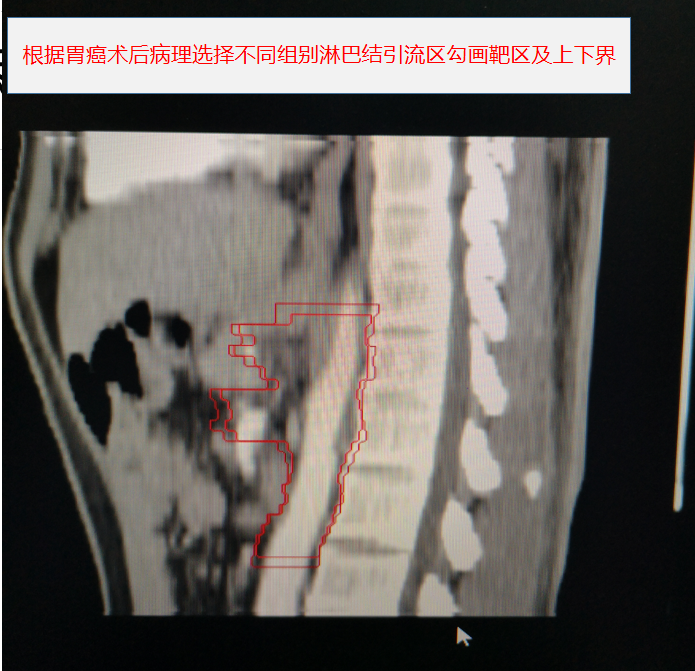

胃癌術後靶區勾畫示例:

其中,胃癌術後規範性預防性放(fàng)療為(wèi)我院首次開展。放(fàng)療前,嚴格按腫瘤放(fàng)療規範和靶區定義勾畫靶區範圍,放(fàng)療期間(jiān),在靶區照射野獲得足夠目标劑量同時(shí),危及器(qì)官受量均在劑量限制标準範圍之内,病人(rén)周圍器(qì)官損傷小,獲益大,實現(xiàn)了(le)真正意義的精準放(fàng)療。放(fàng)療後患者情況穩定,複查各項腫瘤指标均正常,影像學檢查未見異常,得到了(le)上(shàng)級醫(yī)院教授的肯定。